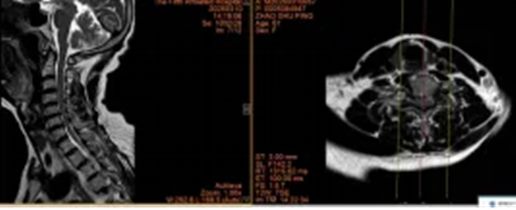

1.东莞市薛先生36岁

640_副本

640 (1)_副本